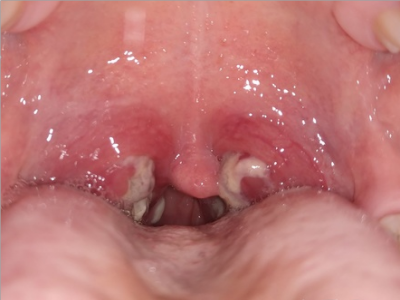

化脓性扁桃体炎扁桃体发红肿胀图

化脓性扁桃体炎患者口咽两侧的扁桃体充血发红,表面没有溃烂面,伴有咽痛,咽痛开始于一侧,继而双侧咽部均明显疼痛,吞咽时明显加剧。